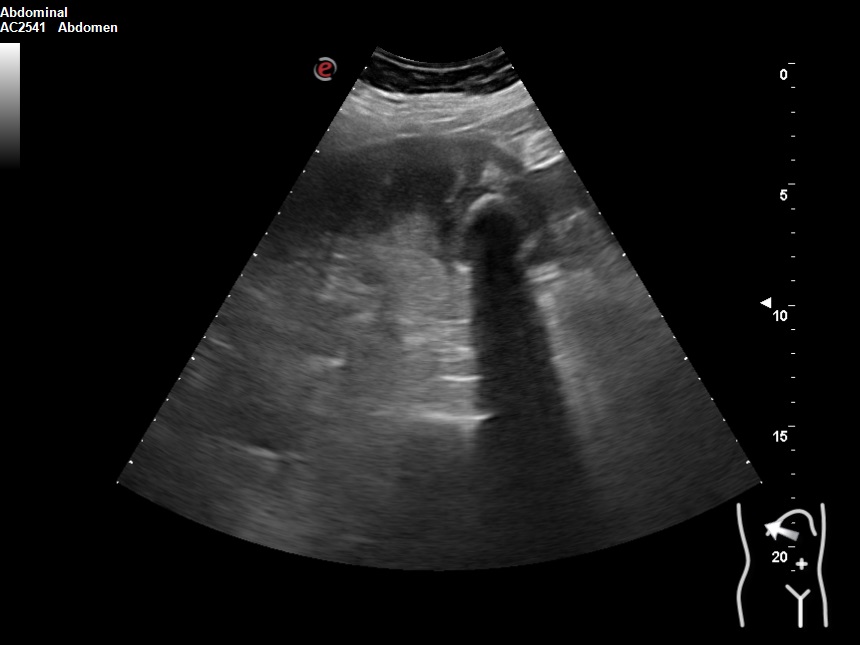

Hallazgos ecográficos

Vesícula biliar desestructurada, de paredes mal definidas con litiasis de 20 mm, que contacta con la pared de la segunda porción duodenal. Porta de tamaño normal. Vía biliar no dilatada.

En los análisis destacaban: GOT 419 GPT 525 FA 373 Bilirrubina 5,3 PCR 184 19.800 leucocitos con neutrofilia. Se realiza tomografía computarizada y nueva ecografía. Se inicia antibioterapia e ingresa con impresión diagnóstica de colecistitis sobre colecsitopatía crónica versus neoplasia vesicular.